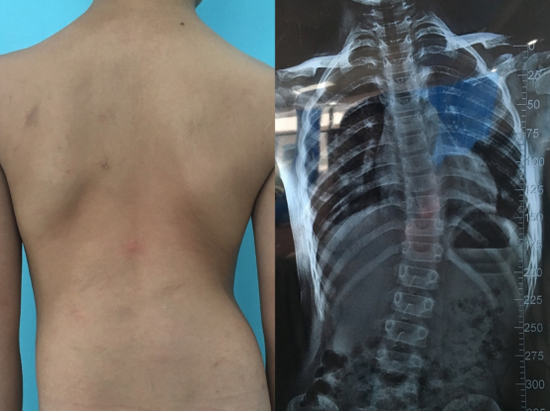

近日,就读于永兴县一中的张同学每天下午从永兴准时到达市第一人民医院西院(康复医院)冲击疗法室,进行脊柱侧弯的调整治疗。12岁的她是一位脊柱侧弯的患者,喜欢长时间低头玩游戏。身体出现了明显的长短脚、圆肩驼背、骨盆发生旋转、严重的影响了其身心健康,给生活带来了很大的困扰!

何为脊柱侧弯? 郴州市第一人民医院(西院)康复治疗部负责人孙伟介绍:脊柱侧弯是一种脊柱的三维畸形,包括冠状位、矢状位和轴位上的序列异常。正常人的脊柱从后面看应该是一条直线,并且躯干两侧对称。如果从正面看有双肩不等高或后面看到有后背左右不平,就应怀疑“脊柱侧弯”。这个时候应拍摄站立位的全脊柱X线片,如果正位X线片显示脊柱有大于10度的侧方弯曲,即可诊断为脊柱侧弯。 脊柱侧弯-危害不可小视! 1、外形方面的影响: 影响了患者骨骼的正常生长发育,使患者出现驼背、鸡胸、骨盆倾斜,肩不等高、背不等平、腿不等长,身体扭曲,身躯矮小等外形的变化。 2、生理方面的影响: 可在凹侧产生骨刺; 压迫脊髓或神经、引起截瘫或椎管狭窄; 严重影响了患者的呼吸系统、消化系统、血液循环系统; 内分泌系统等正常的生理功能、影响寿命; 严重的女性脊柱侧弯患者可能影响生育以及月经不调; 3、精神层面的影响: 小儿多动症和抽动症、青少年焦虑、抑郁症等